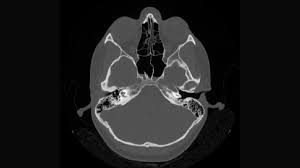

One day, while browsing online for answers, Raj stumbled upon a medical facility offering advanced Sinus CT Scans. He learned that a Sinus CT Scan is a specialized imaging procedure that provides a detailed view of the sinuses, helping in accurately diagnosing issues like chronic sinusitis, nasal polyps, and other structural abnormalities that could be causing his symptoms. Intrigued and hopeful, Raj decided to give it a try.

The scan revealed that Raj had a deviated septum and nasal polyps, conditions that were contributing to his chronic sinusitis. Armed with this new knowledge, Raj’s ENT specialist was able to devise a targeted treatment plan, which included a combination of medication and a minimally invasive surgery to correct the septum deviation and remove the polyps.